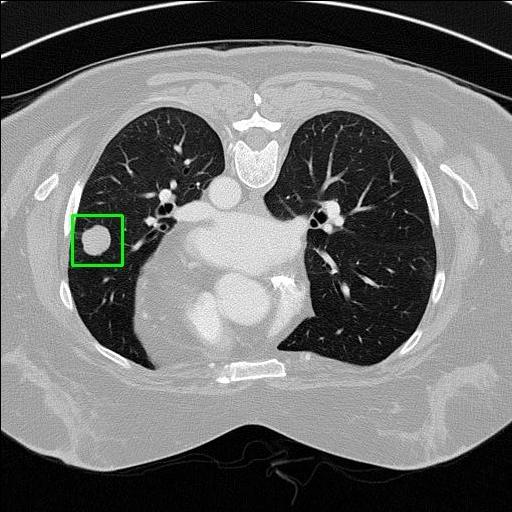

We developed an AI-based system using deep learning models for analyzing lung CT scans to detect and classify pulmonary nodules. We chose the YOLOv11 architecture for its enhanced object detection capability and adapted it specifically for medical imaging, incorporating pixel-level precision and severity classification.

Classification into three severity levels with colored bounding boxes.

Successfully built and deployed an AI model (YOLOv11) capable of detecting lung nodules in CT scans with high accuracy and real-time performance.

Designed a severity classification system that categorizes nodules into null, moderate, and severe using colored bounding boxes, assisting in rapid clinical decision-making.